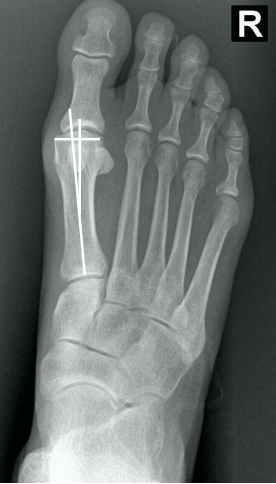

• Na avaliação radiográfica em AP com carga, quais os principais ângulos a serem traçados?

• Ângulo de valgismo do hálux (metatarsofalângico)

• Ângulo intermetatarsal

• Ângulo de valgismo interfalângico do hálux

• Ângulo articular metatarsal distal (AAMD)

• Na radiografia em AP com carga, como é traçado o ângulo intermetatarsal?

• Ângulo entre o eixo longo do 1° e do 2° raio

• Normal → até 9°

• Leve → 9° a 12°

• Moderado → 13° a 15°

• Grave → > 16°

• Na radiografia em AP com carga, como é traçado o ângulo de valgismo do hálux (metatarsofalângico)?

• Ângulo entre o eixo longo do 1° mtt e o eixo longo da falange proximal

• Normal → até 15°

• Leve → < 25°

• Moderado → 25° a 40°

• Grave → > 40°

• Classificação de Mann e Coughlin:

Se baseia nos ângulos radiográficos

• Legenda:

• AVH = ângulo de valgismo do hálux (metatarsofalângico)

• AIM = ângulo intermetatarsico

• Bizu → Memorize o moderado → pra cima é leve e pra baixo é grave